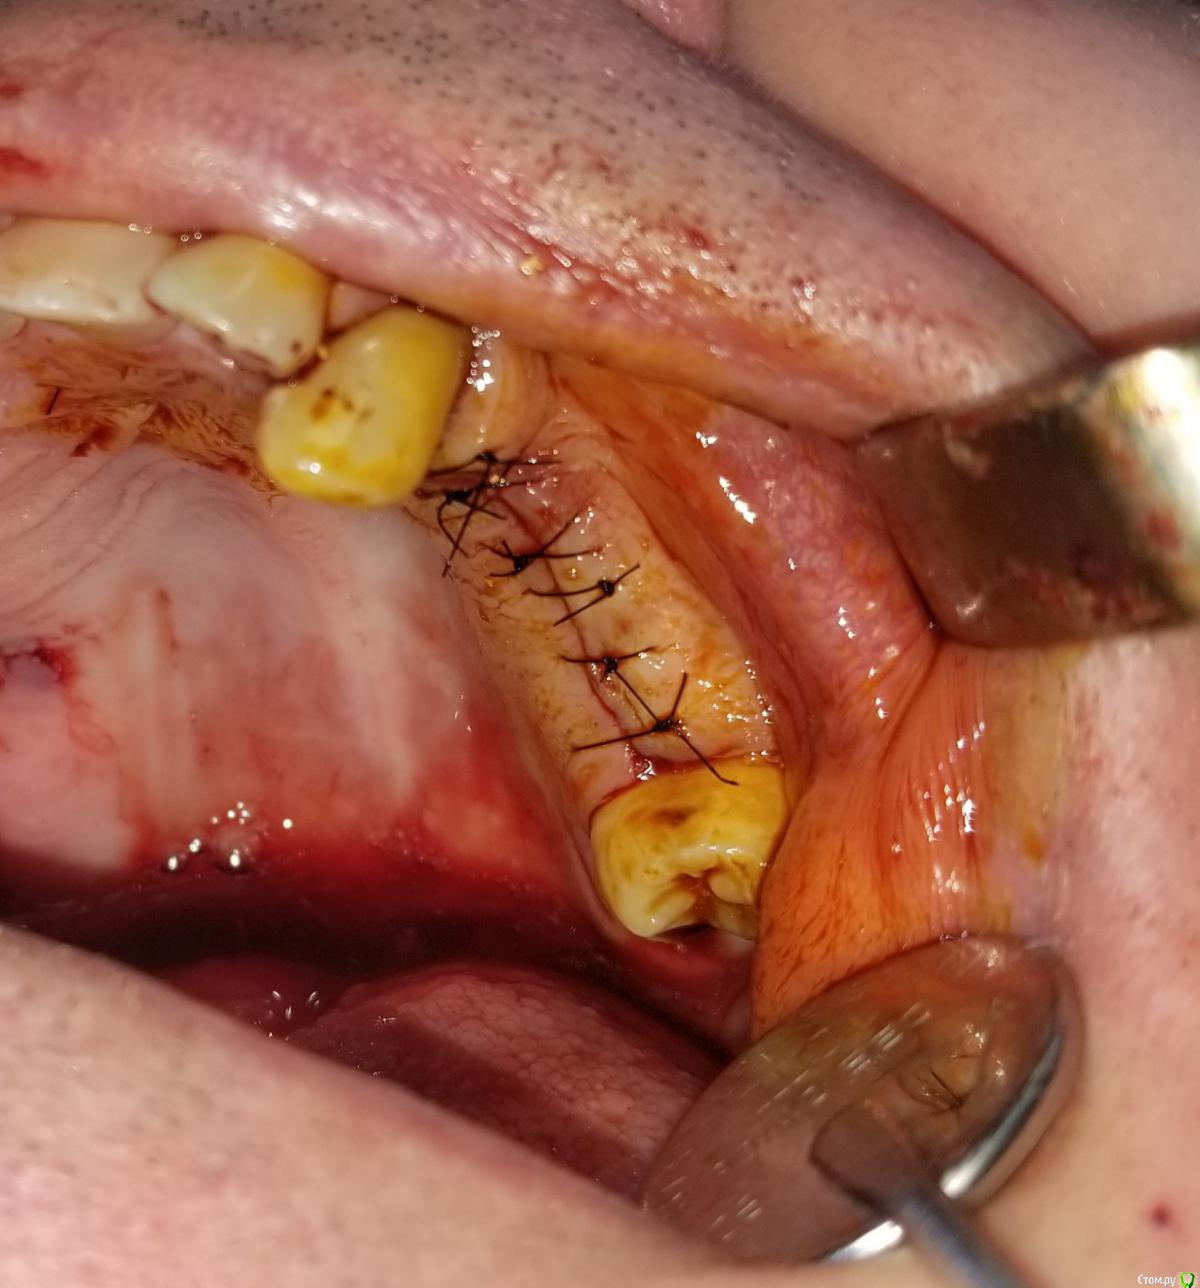

Kostoprav Опубликовано 28 августа, 2020 Поделиться Опубликовано 28 августа, 2020 остеоматрикс+ ауто, укрыто все лоскутом сверху без дополнительных мембран.сделал много таких работ на н\ч и на в\ч- результаты пока очень радуют. 8 Ссылка на комментарий

Snow Doc Опубликовано 1 сентября, 2020 Поделиться Опубликовано 1 сентября, 2020 Кажется взяли кусок титановой сетки и прикрутили заглушкой к болту. А мы тут про сиартбилдеры, спейсеры... И так работает у кого-то) Ссылка на комментарий

Женька Опубликовано 2 сентября, 2020 Поделиться Опубликовано 2 сентября, 2020 Кажется взяли кусок титановой сетки и прикрутили заглушкой к болту. При таком варианте не получится же винт утопить на 1-1.5мм? Ссылка на комментарий